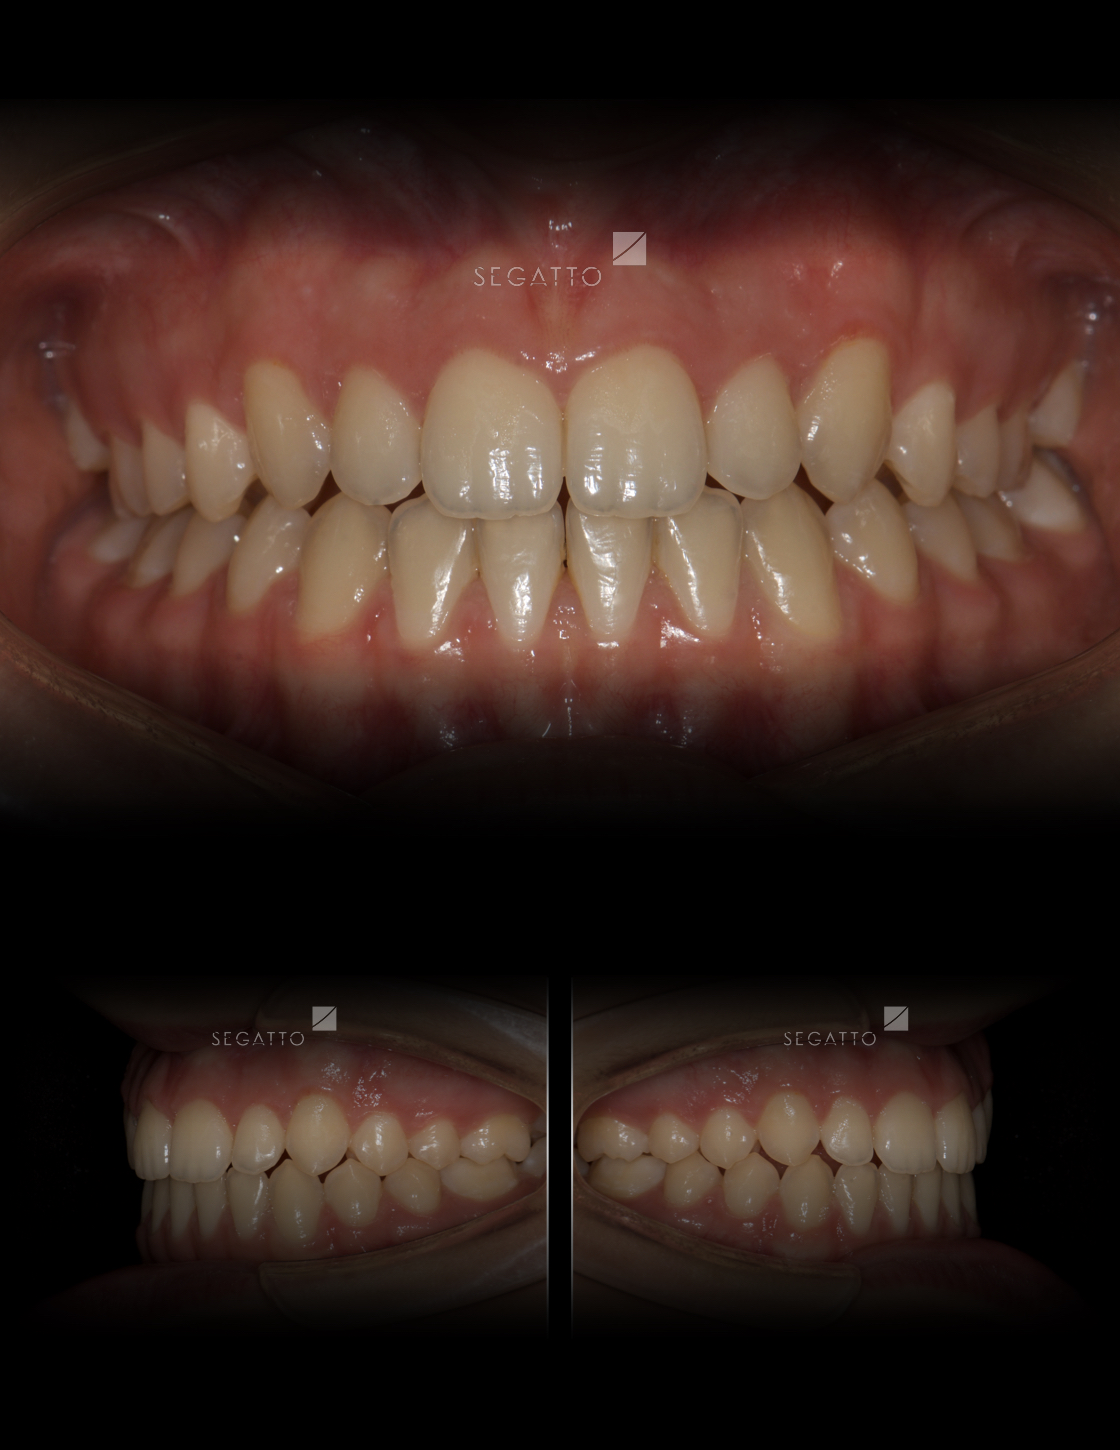

Orthodontics

Cases